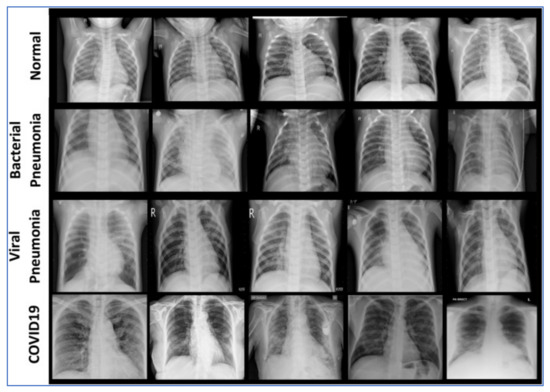

4.1. Feature Extraction Step

4.2. Data Sets